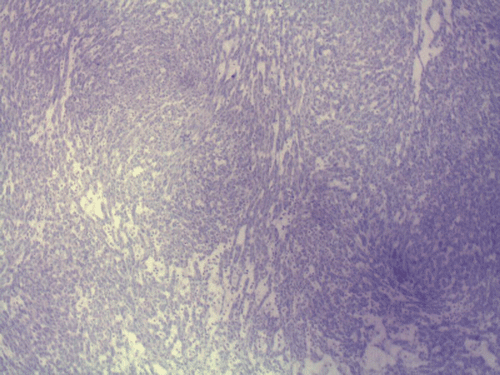

Two major patterns are revealed. In the first pattern, the tumor cells grow in a densely packed tubular pattern with mucinous content (Panel A and B). In some other areas, the tubular pattern is replaced by interlacing fascicles of spindle cells separated by mucinous pools (Panel C and D). In some areas, the spindle cells are solidly packed (Panel E). In both areas, the nuclear are bland in appearance and without significant mitotic acivity. The tumor cells, both in the spindle cell area and tubular areas are strongly positive for cytokerain AE1/AE3, cytokeratin 7, Cam5.2, and epithelial membrane antigen (EMA) respectively (Panel F, G, H and I). The tumor cells are also negative for synaptophysin (Panel J and K) and CD10 (Panel L and M). The positive cells in Panel M are residual non-neoplastic renal tubules. The Ki67 labeling (Panel N) is low (about 1-2%).

These tumors have very characteristic histologic patterns comprised of cuboidal and spindle cells. The cuboidal cells tend to form tubular growth patterns, although trabercular and solid patterns can be identified. Sheets of spindle cells often intersperse between interconnecting tubules, leading to a biphasic appearance. The cells are characterized by eosinophilic cytoplasm, small to medium sized nuclei with little to no atypia, and occasional prominent nucleoli. The surrounding stroma is predominantly myxomatous with a bubbly quality and stains consistently with alcian blue. Studies have shown that a wide majority of MTSCC tumors are positive for epithelial membrane antigen (EMA), AE1/AE3, and cytokeratin 7. In contrast to the classic type of renal cell carcinoma, only about 15% of these tumors are positive for CD10 5. Expression of neuroendocrine markers has also been demonstrated in some tumors 6, 7. Other immunohistochemical markers may be variably positive, including E-cadherin, vimentin, and Ulex Europeus agglutinin-1 (UEA-1). These tumors have a low MIB-1 labeling index. In general, there is not a single marker that could confidently separate this tumor from other renal tumor. The final diagnosis must rest on considerations of morphological and immunohistochemical evidence.